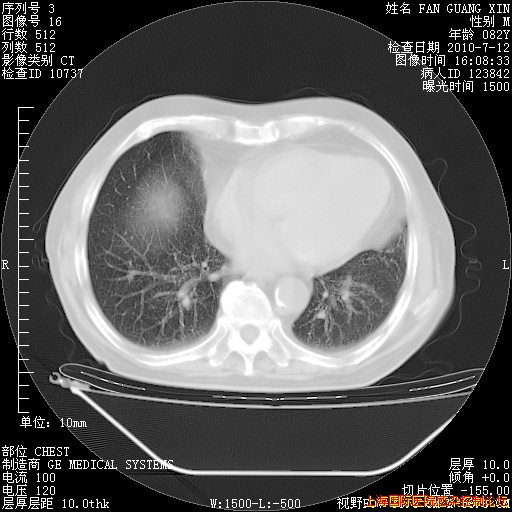

今天复查CT

今天CT

整整相隔30天的肺部CT好像有所好转啊。甲强龙减量第3天,需要观察体温。